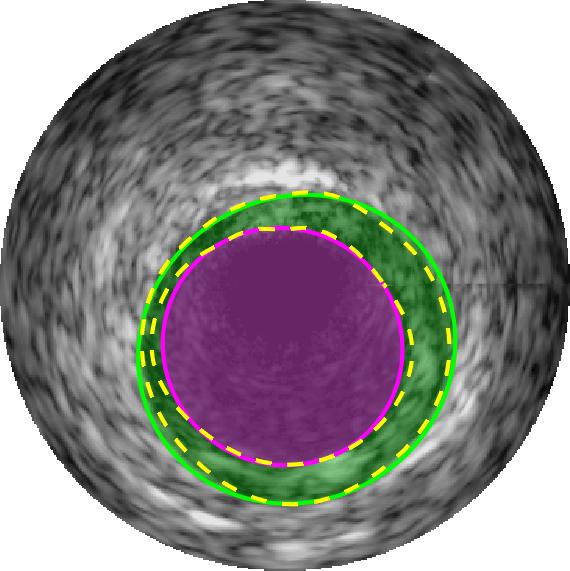

Qualitative evaluations are illustrated in Figure 4 and show the successful segmentation results of the proposed EREL selection strategy for 20 IVUS frames. The lumen areas are highlighted by the magenta colour while the media regions are green. Also, the manually annotated contours for both lumen and media are drawn as yellow dashed lines. As we can see, the chosen frames contain a variety of lumen and media morphologies.